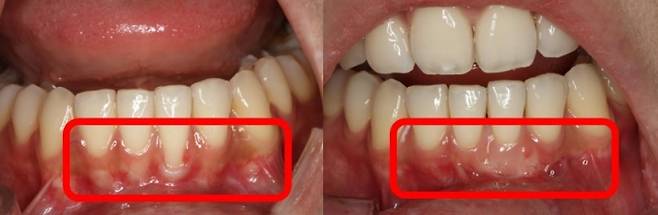

A씨처럼 잇몸 조직이 소실되며 치아 뿌리 방향으로 치아와 치은 부착 부위가 이동하는 현상을 '치은퇴축'이라고 한다. 한 번 내려앉은 잇몸은 심미적 문제 외에도 통증을 동반할 수 있다.

치은퇴축의 치료법으로는 퇴축된 부위 아래, 측면부의 잇몸을 이동시키는 잇몸 성형술과 잇몸 이식술 등이 대표적이다. 잇몸 이식술은 구개(입천장)에서 충분한 양의 결합조직 이식편을 채취해 퇴축 부위를 덮는 방식이다. 이를 통해 노출된 치아 뿌리를 덮고, 잇몸의 높이·부피를 회복할 수 있다. 하지만 이에 앞서, 잇몸질환으로 인해 전반적인 치조골 소실, 치은퇴축 양상이 관찰되면 철저한 치주 치료로 퇴축이 더 진행하는 것을 막는 게 중요하다.